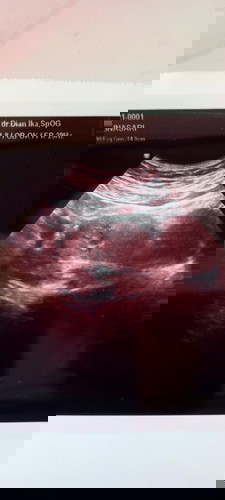

Ini hsil USG janin sy. Bisa dijelaskan apa memang sdh terlihat td kehamilan kt dokter usia 6 minggu

Usia janin 6minggu

kantung janin kelihatan nya